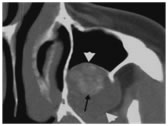

Figure 6: Dentigerous cyst. (A) Coronal bone CT shows a large cystic mass extending from around the crown and cemental- enamel junction (CEJ, arrows) of an unerupted tooth. The tooth is displaced superiorly, whereas the leading edge of the cyst has displaced surrounding unerupted teeth inferiorly. (B) Axial T1- weighted magnetic resonance (MR) image of a dentigerous cyst shows a sharply marginated hyper-intense cystic mass (long arrow). Compare the hyperintensity of the cyst with the iso-intense (cf. muscle) signal of the associated mucosal thickening in the maxillary sinus (short arrow).